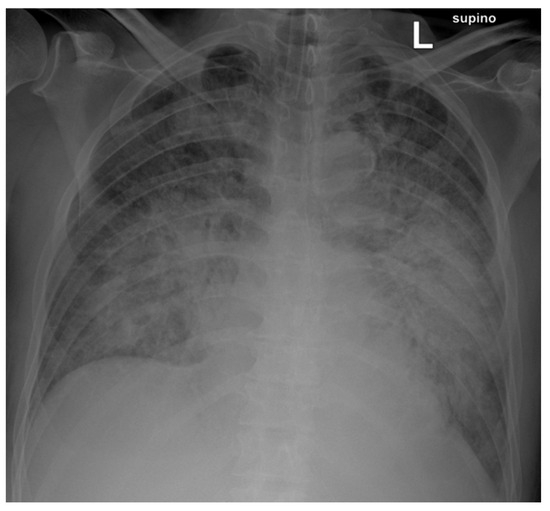

3. Case Report Description